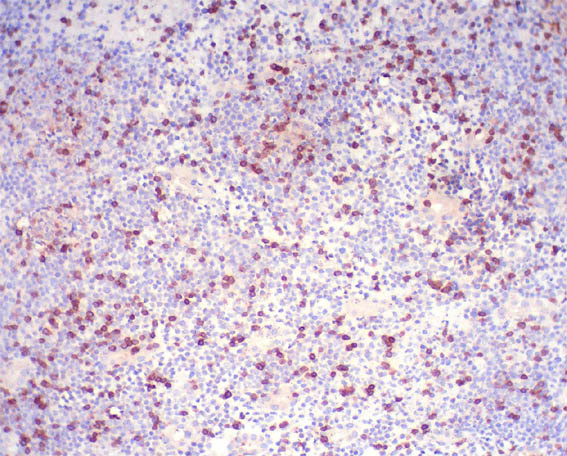

Figure 11. Immunohistochemistry for CD3, X200.